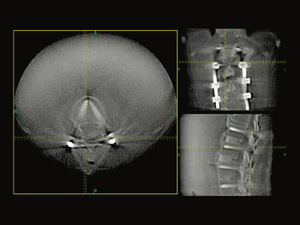

2025年5月には、脊椎手術の安全性をより高めるために、手術支援機器O-arm(オーアーム)を導入し、更に安全な治療が期待できるようになりました。(山形県の医療機関では初導入)。